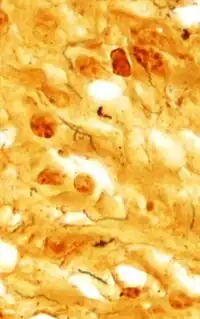

Dieterle stain showing Treponema pallidum(in black), the organism that causes syphilis.

The Dieterle stain is a way of marking tissue for microscopic examination. The key reagent of Dieterle stain is silver nitrate. It can stain microbes like Treponema pallidum in grey or black and background in yellow.[1][2]

It is used to find the organisms that cause cat-scratch disease (Bartonella henselae) and syphilis (Treponema pallidum) and sensitive for Mycobacterium tuberculosis.[3]